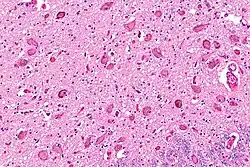

Micrograph showing the locus coeruleus. HE-LFB stain.